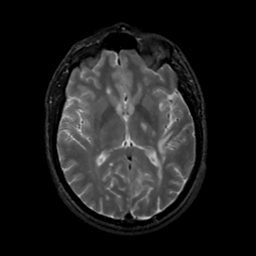

MR Study #13, May 19, 1991 -- Slice #26